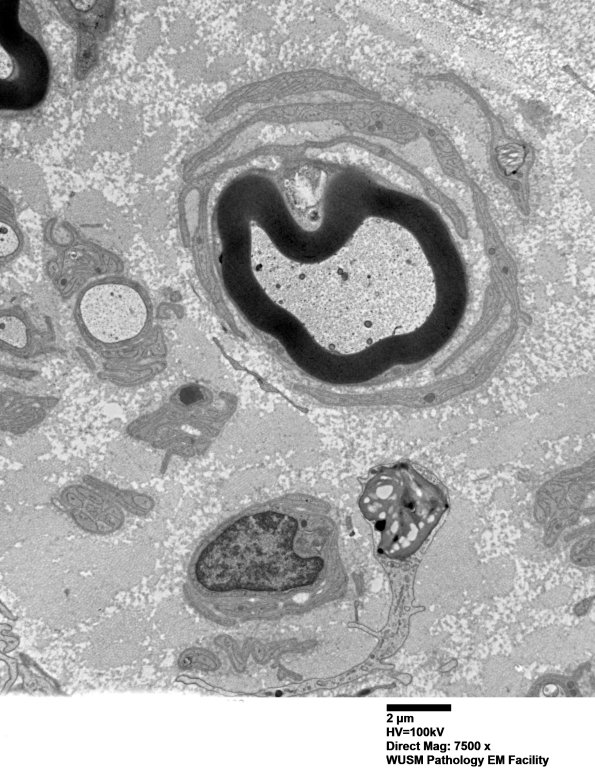

Washington University Experience | PERIPHERAL NEUROPATHY | 20 PSEUDO-ONION BULBS | 6C4 (Case 6) EM038 - Copy

A number of myelinated axons, not compellingly demyelinated, are surrounded by Schwann cell processes forming POB. There are numerous unmyelinated axons which are represented in many cases by “singletons” (single unmyelinated axons per Schwann cell unit). There are numerous bands of Büngner, some with lipidic debris and scattered lipofuscin. There are numerous axons with thinned myelin for axon caliber and regenerative clusters, evidence of axon degeneration with regeneration. Genuine onion bulbs are not present, nor are demyelinated axons, macrophage mediated demyelination or significant inflammation.